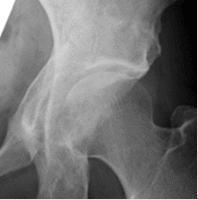

変形性股関節症は軟骨がすり減る疾患で、歩行や立ち上がりに痛みを感じます。レントゲンですり減りの程度がわかりますが、レントゲンで変形が強くても自覚症状が乏しいことがあります。鎮痛剤やリハビリなどの保存療法を行いますが、鎮痛剤がなくては生活できない方、痛みが強く日常生活に支障をきたしている方、レントゲンで変形が著しい方は手術をお勧めします。手術は軟骨損傷の程度によって関節鏡手術、骨切手術、人工関節置換術があります。

臼蓋形成不全やそれに伴う軽度の変形のために、長時間歩行で脚がだる痛くなるなどの症状を訴える患者さんに対しては、リハビリなどの保存療法で改善しない場合に、臼蓋形成術および寛骨臼回転骨切術という2種類の手術療法で対応しております。いずれの手術を行うかは、年齢、股関節の変形の程度、社会的状況を考慮して決めさせていただいております。いずれの手術でも術後1週間程度で車椅子移乗が可能となり、1ヶ月から2ヶ月程度で退院が可能となります。

24歳、臼蓋形成術後2年

43歳、寛骨臼回転骨切術後2年